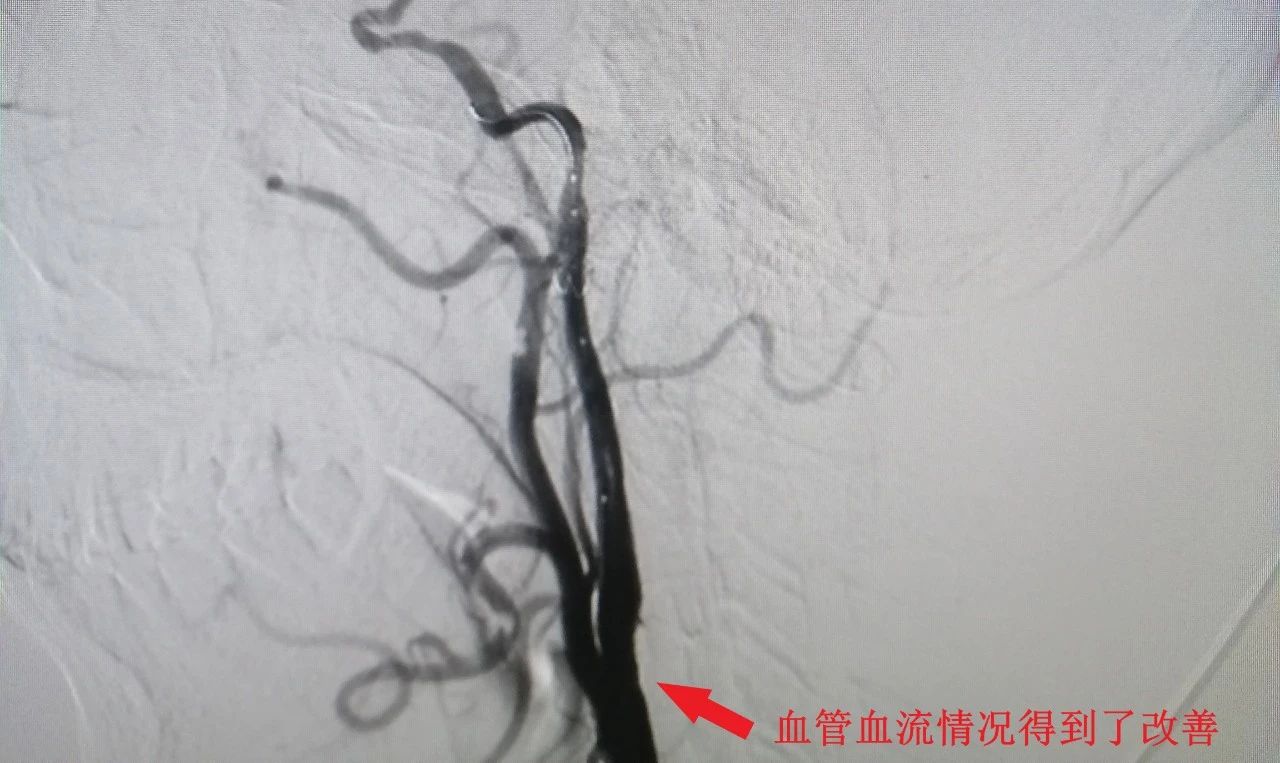

在介入团队密切协作下,手术顺利完成。术后,患者血管血流情况得到了改善。

支架植入后血管狭窄解除

颈动脉重度狭窄血管处植入支架,小小支架撑开了狭窄的颈内动脉,使脑血管畅通无阻。